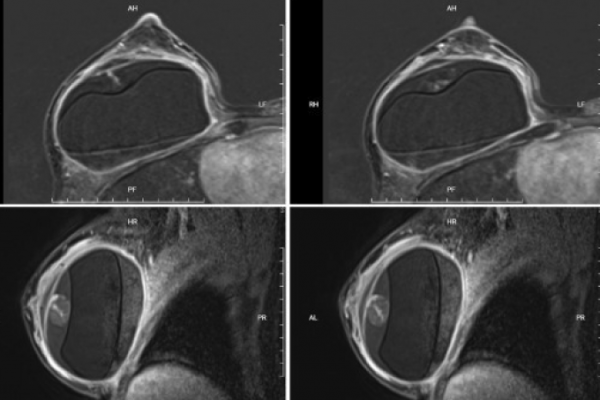

15 năm nâng ngực: Biến chứng tụ máu quanh túi độn

Những cơn đau ngực bất thường sau nhiều năm nâng ngực có thể là dấu hiệu của biến chứng muộn, một tình trạng hiếm gặp nhưng cần được phát hiện và điều trị kịp thời. Hai trường hợp gần đây tại Bệnh viện Đa khoa Tâm Anh TP HCM đã minh chứng cho điều này….